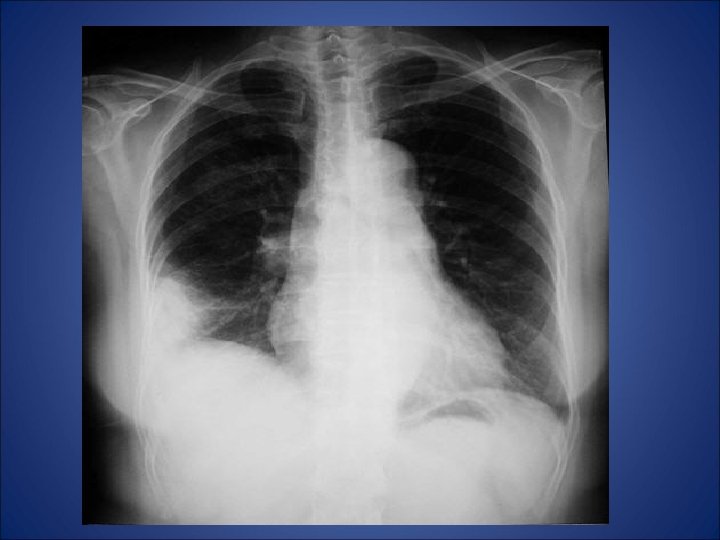

RX toracic

• Care este diagnosticul pacientului?

Embolism pulmonar acut • - desi simptomele clinice indica embolismul pulmonar (durere pleuritica, dispnee), pacientul din cazul de fata nu prezinta niciun factor de risc (chiar mai mult ca factori de preventie avem varsta si activitatea fizica) - pentru certitudine s-a folosit investigatia CT care a relevat multipli emboli atat in vascularizatia majora a plamanului stang cat si a celui drept - orice evaluarea ulterioara a pacientului nu a putut elucida cauza embolismului. • Nu exista suficiente referiri la naproxen in cazurile raportate de embolism pulmonar si astfel nu poate fi incriminat pentru producerea acestui fenomen. Mai mult, dupa tratamentul intraspitalicesc pacientul a refuzat tratamentul cu warfarina si la la cateva luni au aparut alte episoade de embolism. Decizia terapeutica finala a fost plasarea unui filtru Greenfield de vena cava inferioara.